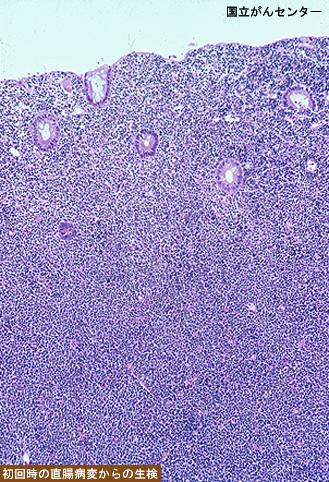

疾病(病理主体)的分类恶性淋巴系肿瘤/恶性淋巴瘤

部位(按器官分)大肠/直肠

检查方法病理切片(微观)

肿瘤的肉眼分类1型(肿瘤型)/

肿瘤最大直径35~40